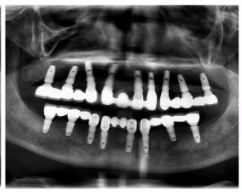

種牙前X光片

種植修復(fù)后X光片